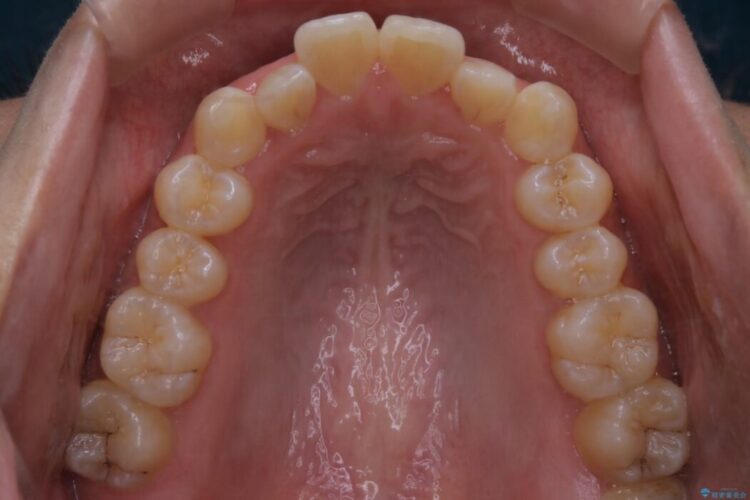

前歯の一部に反対咬合が見られ歯列がガタガタしていたためインビザラインでの矯正治療をご提案しました。

また、奥歯の噛み合わせなどにほとんど問題がなかったことからインビザラインのライトパッケージを選択しました。